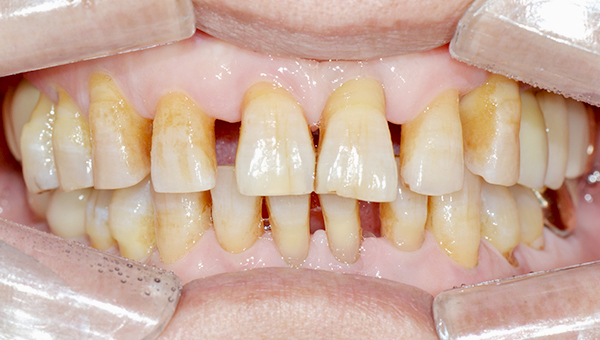

심*복 임플란트 시술 사례

전체 임플란트

2024.12.05

치료 전

2025.05.30

치료 후